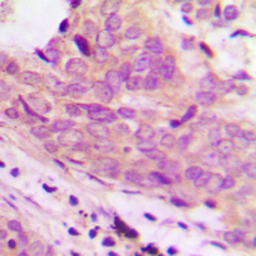

IHC-P analysis of formalin fixed human prostate cancer tissue section using GTX56127 MARCH-I antibody.

Antigen retrieval : Heat mediated antigen retrieval with sodium citrate buffer (pH 6.0)